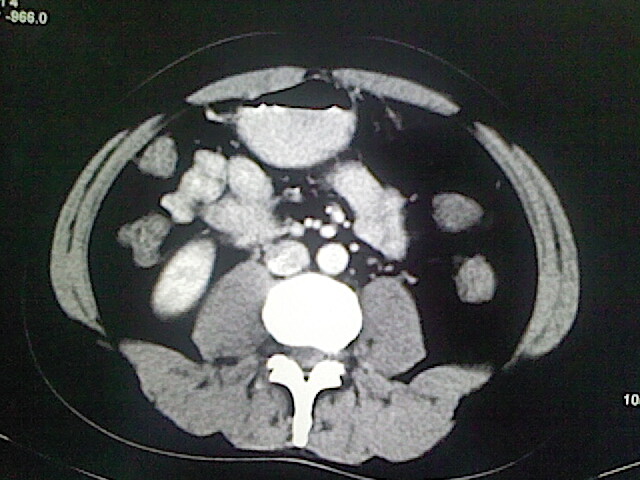

以下是引用卜一在2009-3-14 9:49:00的发言:[br]胆囊萎缩,胆囊壁不规则增厚,内部结构模糊,增强明显强化。另:肝左叶外侧段肝囊肿。支持:慢性胆囊炎!高度可疑:胆囊癌!

以下是引用余辉在2009-3-14 8:48:00的发言:[br]1)慢性胆囊炎。2)肝左叶外侧段肝囊肿。3)脂肪肝。[br]支持,胆囊萎缩,密度增高,不知b超具体有何提示,钙胆汁?结石?

以下是引用jiangjing在2009-3-14 10:18:00的发言:[br]1)慢性胆囊炎。2)肝左叶外侧段肝囊肿。3)脂肪肝。4.】建议行肝功能检查